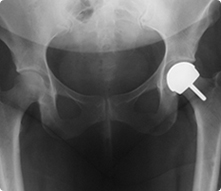

Birmingham Hip Resurfacing X Ray Birmingham Hip Resurfacing System

Birmingham Hip ResurfacingThe Birmingham Hip Resurfacing (BHR) is a metal-on-metal prosthesis used in hip resurfacing procedures. Hip Resurfacing is a bone conserving procedure where the acetabulum (hip socket) is replaced and femoral head is resurfaced. Hip resurfacing is indicated in individuals with arthritis where conservative treatment has failed. The advantage of the hip resurfacing procedure is that the femoral head is preserved.  Some studies indicate that the loading of the femur is closer to normal with this procedure.

In hip resurfacing, the articular surfaces of the femur and acetabulum are replaced. The procedure is bone conserving as most of the head of the femur is retained. Instead of removing the head completely as with a total hip replacement, it is shaped to accept a low-wear metal sphere. This sphere matches the patient's own anatomy that confers low risk of dislocation, a broad range of movement and excellent stability.

The BHR offers a bone conserving  alternative to total hip replacement, with the potential for higher levels of patient activity. The BHR system has allowed many young and active patients, athletes, and sports personalities with arthritic hips to perform their normal activities with no or minimal pain.

Data from the Australian hip registry has indicated better performance of the BHR implant compared to conventional total hip replacement in male patients under the age of 60.  Because the femoral head is not replaced, bone quality must be good enough to support the implant.